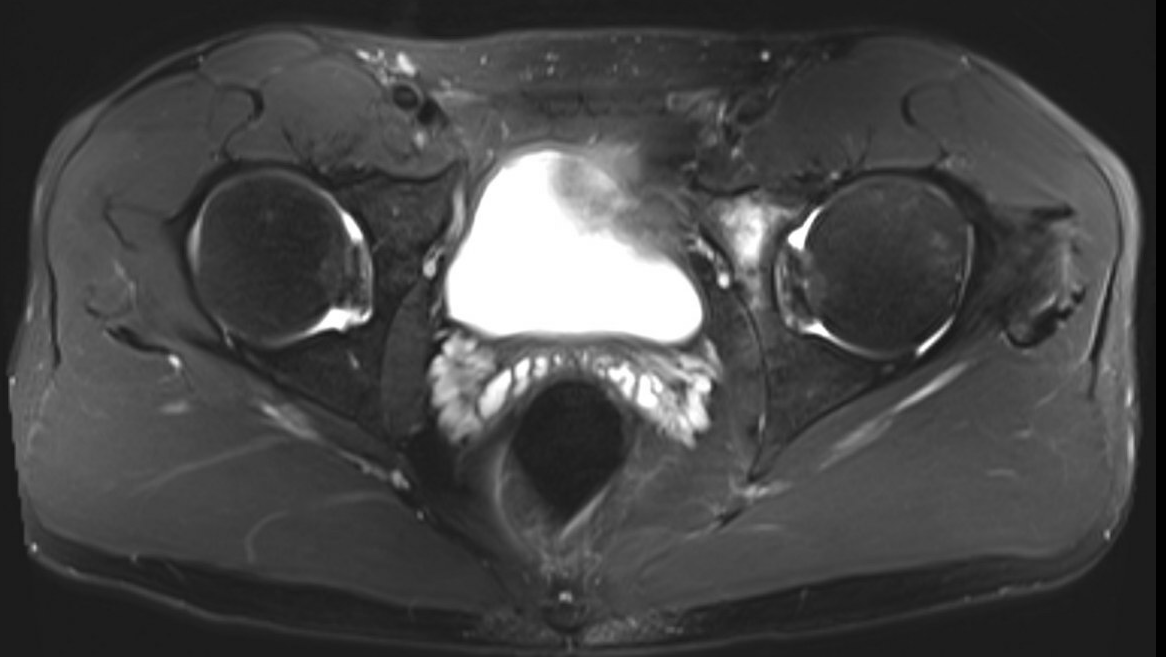

MRI

Labral tears

Best seen on coronal MRI

MRI alpha angle